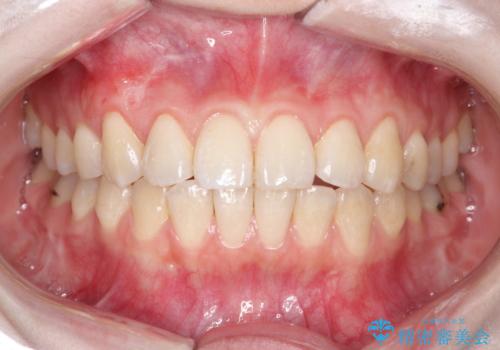

前歯の歯肉退縮 歯周形成外科(歯冠側移動術)

- 上顎左側側切歯の歯肉退縮を主訴に来院されました。

生活に支障はないが審美的要求が強く歯肉形成外科(歯冠側移動術)を行うこととしました。

根面被覆術には結合組織を用いる場合もありますが、今回のケースでは、角化歯肉が十分あり、審美性の要件が強いため、隣在歯との調和が取りやすい歯冠側移動術のみで対応しております。

結合組織を使用するメリットは術後の後戻りのリスクを減らすことが考えられます。